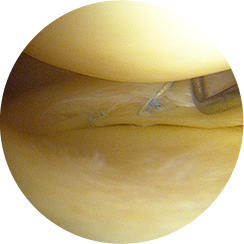

무릎 관절내시경 수술은 1cm 미만의 작은 수술 부위에 내시경과 수술기구를 삽입하여

손상된 연골이나 인대, 이물질 등을 직접 확인하고 정밀하게 치료하는 수술입니다.

관절내시경을 삽입해 내부를 실시간으로 보면서

손상된 부위를 정밀하게 제거하거나 봉합하기 때문에,

CT나 MRI로도 정확히 파악하기 어려운 미세한 연골 손상이나

관절 내부 이상까지 확인하여 보다 정확한 진단과 즉각적인 치료가 가능합니다.

고해상도 영상으로

연골·인대·반월상연골의

손상 부위를 정확히 확인합니다.